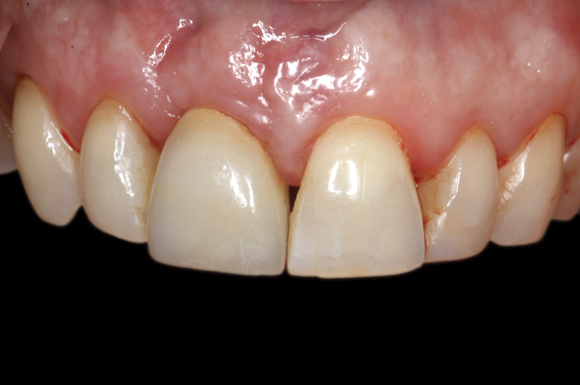

(26.) Facial and occlusal views of the soft-tissue contour achieved after 3 months of provisionalization. The tissue is thick with a harmonious gingival contour and zenith position.

Figure 26

(27.) Facial and occlusal views of the soft-tissue contour achieved after 3 months of provisionalization. The tissue is thick with a harmonious gingival contour and zenith position.

Figure 27

The patient was postoperatively evaluated at 1-, 2-, 4-, 8-, and 12-week recall appointments. The sutures were removed at the 2-week appointment, and the patient was instructed to rinse twice daily and avoid brushing the anterior maxilla. Prior to provisionalization of the implant, the site was allowed to heal for 6 months, during which time the patient was temporized with another Maryland bridge. At the 6-month recall appointment, full mouth periodontal maintenance was completed, and an implant-retained acrylic provisional restoration was placed (Figure 23 through Figure 25). An acrylic provisional restoration allows for soft-tissue attachment while preventing apical migration of the gingival margin. After a 3-month provisionalization period, the final prosthesis was delivered (Figure 26 through Figure 29), and the patient was scheduled for ongoing 3-month recall appointments for periodontal maintenance.